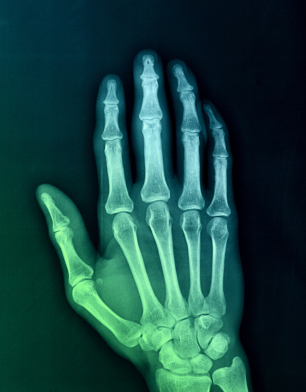

In the third and final segment of neuro.RAPT's three part film series dedicated to Our Hands, Orthopedic Surgeon Dr. Taizoon Baxamusa covers:

1) What is arthritis?

3) How does the body take attempts to stabilize arthritis?

4) Is there a correlation of x-ray images of arthritis and the severity of the symptoms?

5) What is basilar joint arthritis?